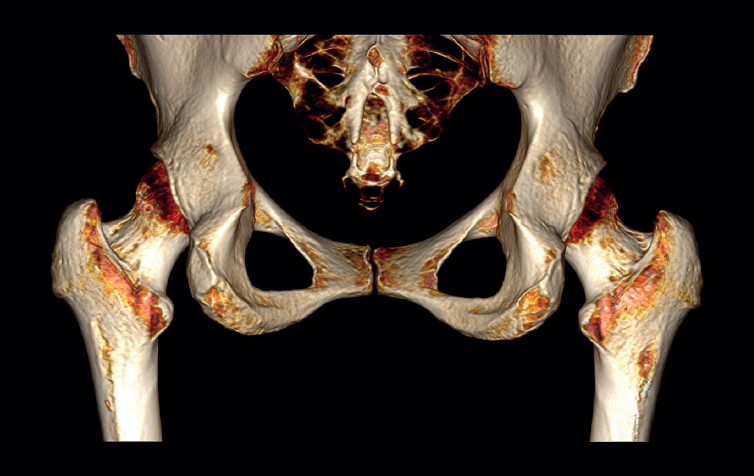

The physical examination revealed a limp-free gait and complete joint balance, with no positive signs of femoroacetabular impingement or inguinal pain. Muscle strength was preserved and similar to that of the contralateral side. She experienced intense pain on palpation of the insertion of the gluteus maximus, referred proximally to the ipsilateral buttock. The pain was reproduced on extension against resistance, and prevented sitting for long periods. Plain radiographic and computed tomography (CT) images revealed calcific tendinosis affecting the aponeurotic prolongation of the gluteus maximus in proximity to its insertion in the upper region of the linea aspera of the femur (Figures 1 and 2) Magnetic resonance imaging (MRI) of the hip showed a labral tear, that proved asymptomatic in the physical examination. In view of the clinical picture of radicular pain, an MRI scan of the lumbar spine and subgluteal space was also performed, ruling out radicular involvement or sciatic neuritis. Her previous treatment over the three years of evolution of the disorder included oral nonsteroidal anti-inflammatory drugs, a specific physiotherapy programme and several ultrasound-guided corticosteroid injections with positive results - though a last session showed no response. Due to the severity and chronicity of the symptoms and their resistance to conservative treatment, surgery was decided to clean and remove the intratendon calcification endoscopically.

A usual rehabilitation protocol after hip arthroscopy / endoscopy was applied, with crutch-assisted weight bearing for three weeks and circumduction movements plus stationary cycling for 15 minutes, four times a day. The patient was advised to avoid extension and long stride exercises in order to prevent possible gluteus maximus tendon injuries. She reported complete reversal of the symptoms, including the radicular pain, with a return to physical activity and sports three months after surgery. One year after the operation, the patient remained asymptomatic in any activity, with complete disappearance and no recurrence of the calcification (Figure 4).